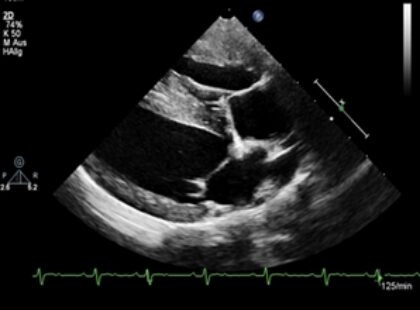

Die Echokardiographie des rechten Herzens stellt auf Grund der Morphologie meist eine Herausforderung dar. Zahlreiche Erkrankungen sowohl kongenital (z.B. Pulmonalstenose, Trikuspidalklappendysplasie, ASD), als auch erworben (z.B. Trikuspidalklappeninsuffizienz, ARVC, pulmonaler Hochdruck, Herzwürmer) spielen aber in der Praxis inzwischen eine wichtige Rolle und können echokardiographisch diagnostiziert und auch in ihrem Schweregrad bewertet werden.

Hierfür stehen verschiedene Rechtsherzparameter beginnend mit einem normalen Vierkammerblick, aber auch Funktionsmessungen wie die TAPSE, Bewertung der Pulmonalflussprofile oder ein Einschätzung der rechten Pulmonalarterie (Beweglichkeit und Verhältnis zu der Lungenvene). Ziel ist eine Bewertung welche eine mögliche Therapie (medikamentell oder kausal) nach sich ziehen kann.